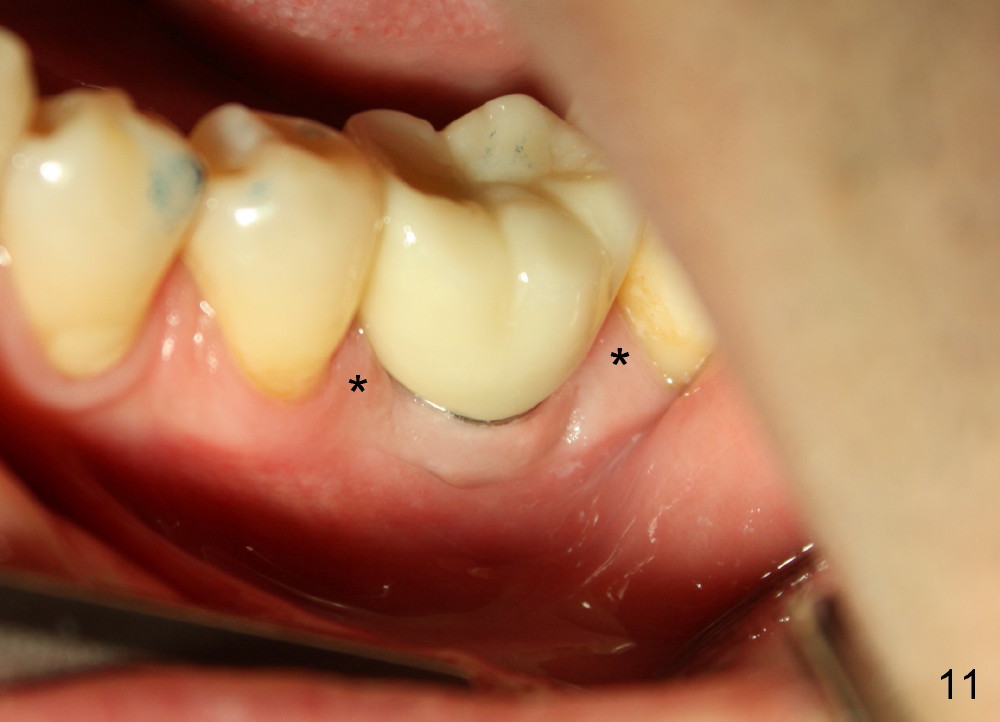

There is a thick gingival band buccal to the implant 7 months postop (Fig.9 *). Osteointegration occurs (Fig.10). The most unexpected finding is the formation of the papillae (Fig.11 *) when the permanent crown is seated. The cosmetic result is due to immediate placement of the large implant. Delayed implant usually cannot achieve this type of outcome.

Two and a half months post cementation, the buccal metal show is much less and confined to the midbuccal portion. It appears that the papillae increase their mesiodistal dimension (data not shown). Bone appears to remain stable over the implant surface 2.5 and 9 months post cementation (Fig.12 >,13). The papillae around the implant crown remain normal 11 months post cementation (Fig.14 *). No bone loss is noticed 26 (Fig.15) or 38 (Fig.16) months post cementation. There is no bone loss around the 7x17 mm tissue-level implant 6 years 8 months post cementation (Fig.17).